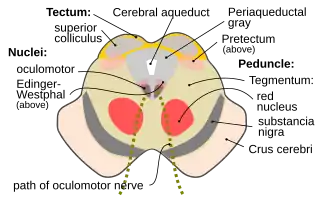

Вокруг водопровода располагается центральное серое вещество, в котором заложены ретикулярная формация, ядра III и ядра IV пар черепных нервов и др. На сечениях среднего мозга сильвиев водопровод может иметь вид треугольника, ромба или эллипса. Через него происходит циркуляция ликвора (спинномозговой жидкости)[1][2].

У человека представляет собой канал длиной около 15 мм, соединяющий в головном мозгу полость третьего желудочка головного мозга с четвертым[1]. Дорсальную стенку образует пластинка четверохолмия среднего мозга, вентральную — покрышка ножек мозга. Образуется в онтогенезе из полости третьего мозгового пузыря[2].

Вокруг Сильвиева водопровода находится центральное серое вещество (substantia grisea centralis)[2], анатомически относящееся к покрышке среднего мозга. Это серое вещество направляет свои восходящие проекции в ядра шва и в голубое пятно, а также в соматосенсорные и висцеросенсорные ядра таламуса. Оно также имеет нисходящие проекции в спинной мозг. Восходящие нервные волокна спиноталамического пути, проводящие ощущения боли и температуры, на своём пути в таламус делают промежуточную «остановку» в околоводопроводном сером веществе. Эта часть спиноталамического пути называется спиномезэнцефалическим путём. В свою очередь, воспринимающие болевые и температурные ощущения ядра таламуса направляют свои нисходящие волокна обратной связи к спинному мозгу также через центральное серое вещество. В центральном сером веществе в области дна водопровода располагаются ядра двух пар черепных нервов. на уровне верхних холмиков четверохолмия среднего мозга, ближе к срединной линии залегает парное ядро глазодвигательного нерва (III пара черепных нервов). Вентральнее от него залегает добавочное ядро глазодвигательного нерва (n. oculomotorius accessorius) — ядро Якубовича (Ядро Эдингера-Вестфаля). Несколько выше и кпереди от ядра глазодвигательного нерва залегает одно из ядер ретикулярной формации — промежуточное ядро (nucleus interstitialis, ядро Кахаля)[2].

Поперечный разрез среднего мозга. Цифрой 2 показан водопровод мозга

Поперечный разрез среднего мозга на уровне нижнего двухолмия. Поперечный разрез среднего мозга на уровне верхнего двухолмия.